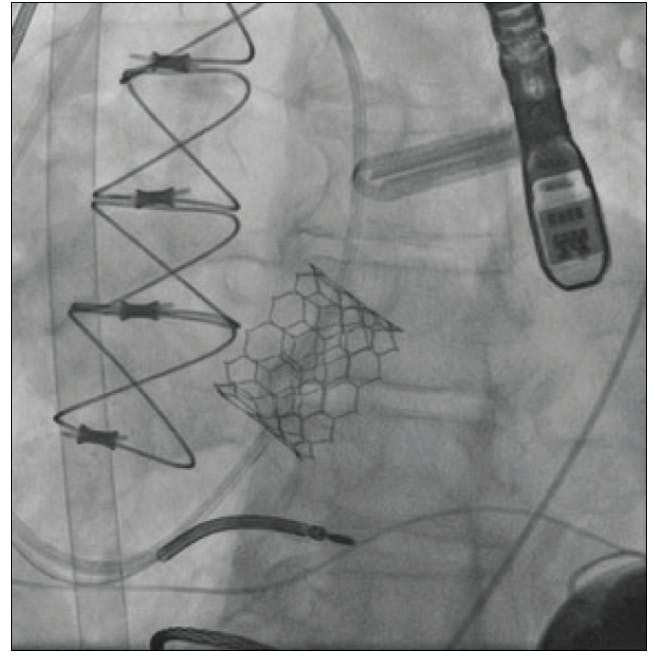

Device migration was also prominent in Yehya et al; nine patients with continuous-flow LV assist devices (CF-LVADs) underwent TAVR for AI, and 22% of patients required a second implant.13,14 Instead of a modified Park stitch, patch closure, SAVR, or Amplatzer device (Abbott), TAVR can be used in CF-LVAD patients with AI from static flow and altered hemodynamics (Figure 1). Concomitant treatment of existing greater than mild AI is recommended at the time of CF-LVAD placement and postimplantation; untreated AI will dampen device performance.13,14 In these extreme-risk surgical patients, a less invasive method of treatment is preferred. The results of Yehya et al were promising, with a decrease in AI to none/trace in all nine participants (Figure 2), 100% survival to discharge, and 89% survival at 6 months.13,14 However, along with migration, bleeding-related complications also occurred. One-third of patients had access site/vascular complications, and although not existent in this study, TAVR thrombosis for AI in CF-LVAD has been reported.13-15

Figure 1. Angiography of a CF-LVAD patient who received a balloon-expandable valve for AI.